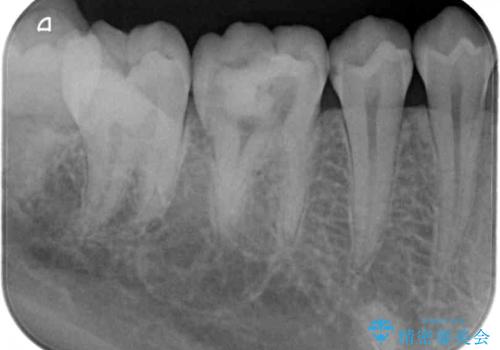

放置した虫歯 根管治療とオールセラミッククラウン

- 奥歯の虫歯を放置してしまい、痛みを感じることがあるとのことで来院された患者様です。

術前の診査では、神経を取り除かなくても済む可能性が示唆されましたが、実際に虫歯除去を進めたところ、レントゲン写真から読み取れる通り、神経組織にまで虫歯が及んでいることが分かりました。

速やかにラバーダム下にて根管治療を行うこととし、その後オールセラミッククラウンにて補綴治療を行うこととしました。